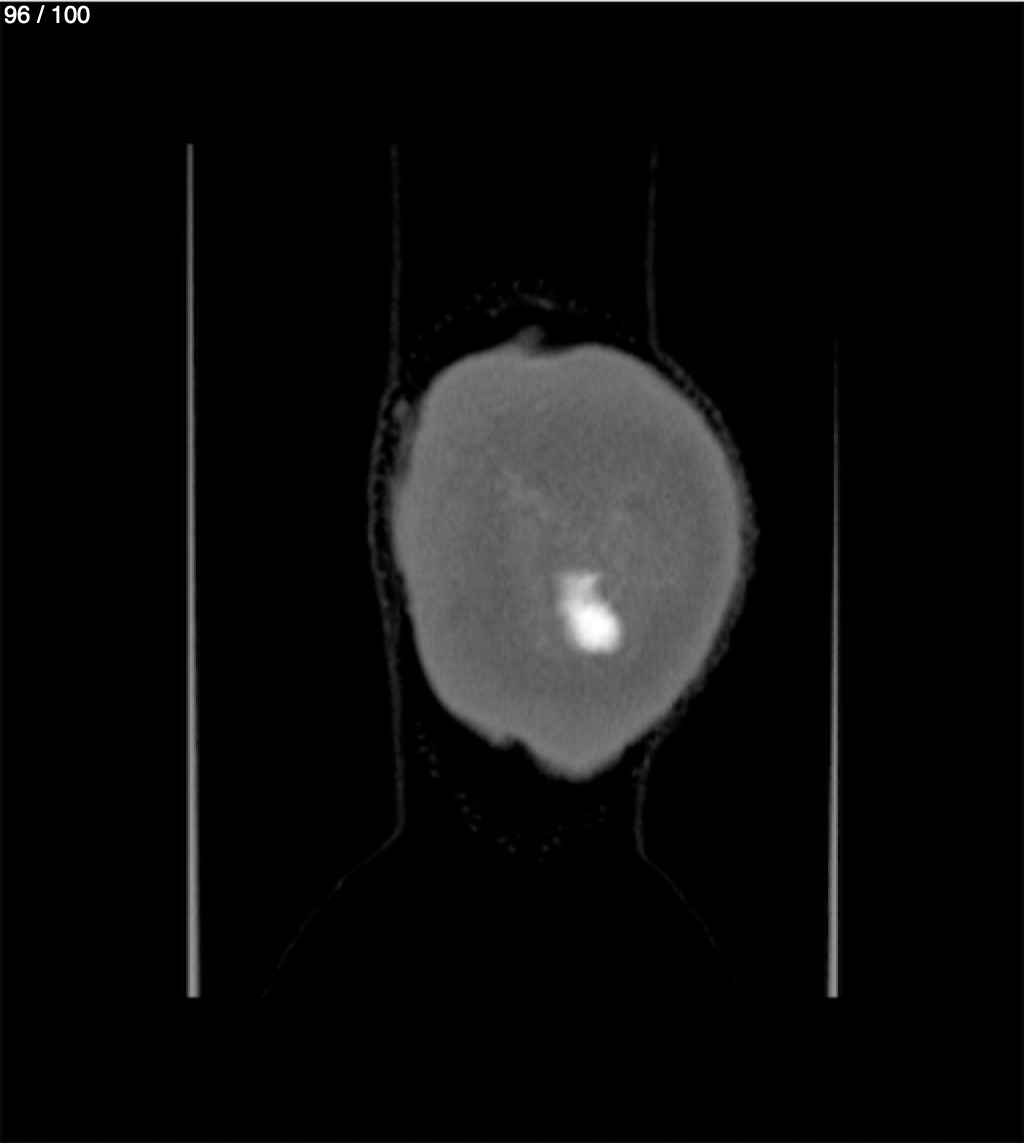

Yonelly Barrios Diaz 35A - T.C Craneo